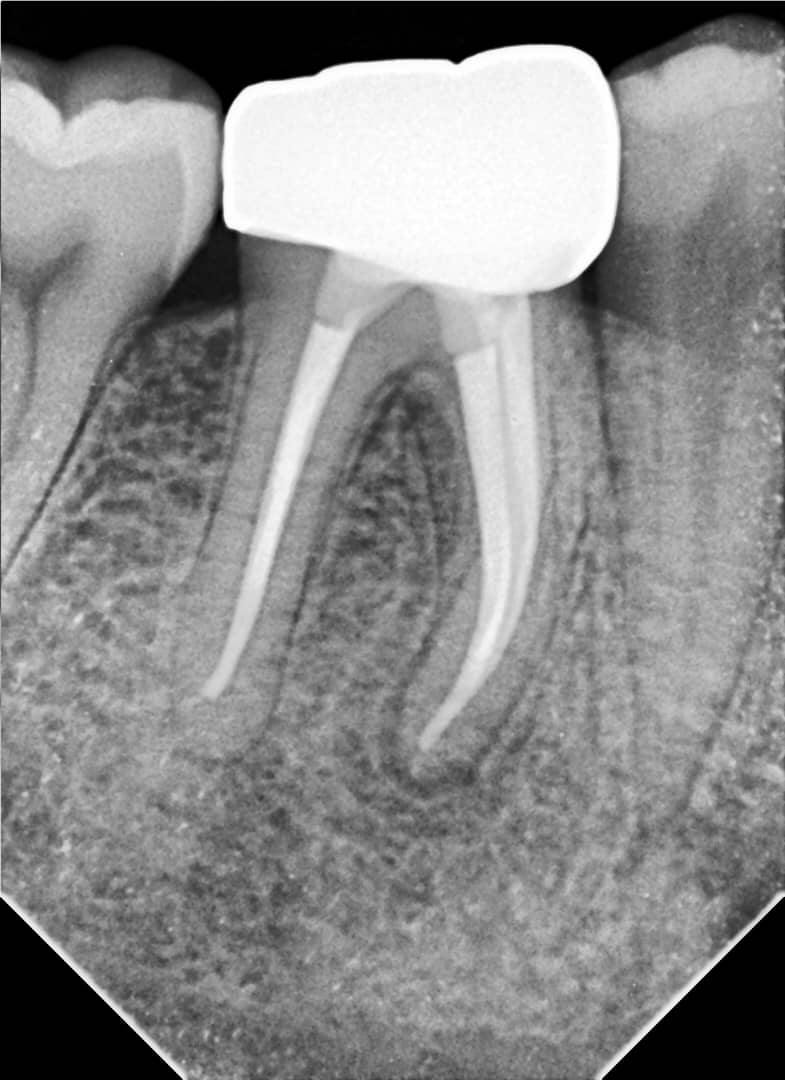

- Obturation with gutta-percha using the lateral condensation technique and AdSeal sealer

- Tooth restored with a zirconia crown

6-month follow-up:

Clinical and radiographic signs indicate successful healing of the periapical tissues.